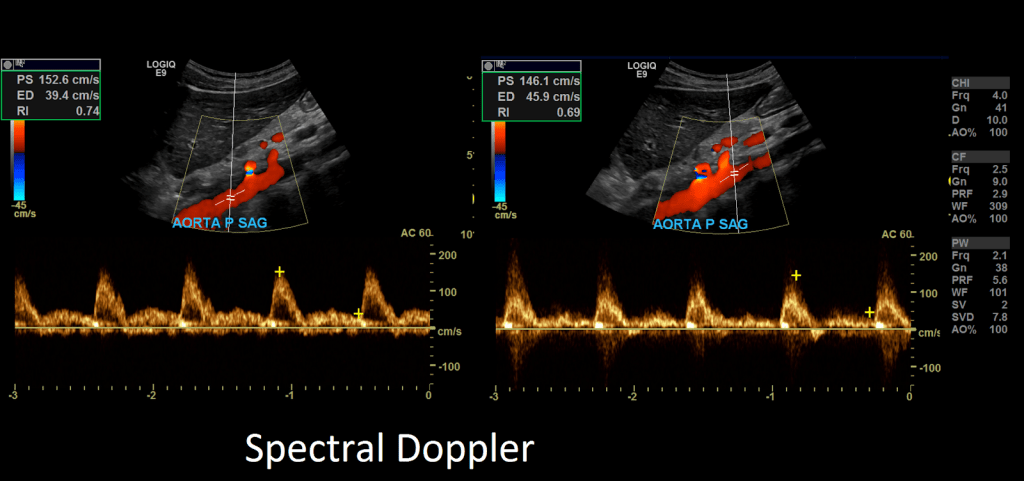

After you’ll want to image the aorta in sagittal and transverse in grayscale and with color and spectral Doppler.

Take gray-scale, color and spectral Doppler of the common iliac artery. Use angle correction 45-60°.

Measure the peak systolic and end diastolic velocities.